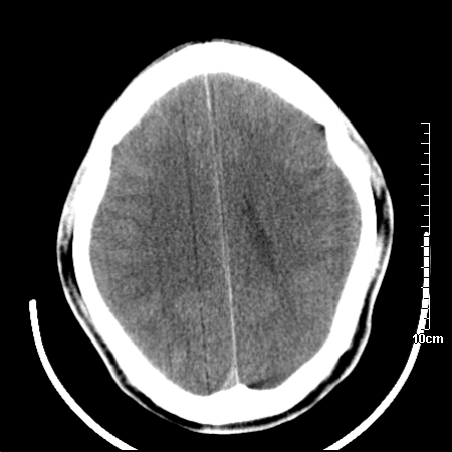

右側额叶、放射冠区灰白质改变,建议ct增强或mri检查

右侧放射冠区混杂密度灶,边缘不清,病人较年轻,结合有发热病史,支持感染性病变,建议密切结合临床可抗感染治疗后复查。

右侧颞叶病变定性困难,既然发病急,又有发热,脑脓肿不能除外。

右侧颞叶混杂密度灶,强烈建议:增强ct检查